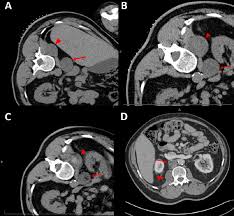

Malignant Peripheral Nerve Sheath Tumor Of The Transverse Colon With Peritoneal Metastasis A Case Report Journal Of Medical Case Reports Full Text

Surgeons carefully remove your schwannoma while taking care to preserve nerve fascicles that arent affected by your tumor. Rarely nerve sheath tumors can be malignant. On conventional MRI and diffusion-weighted imaging DWI MPNSTs and BPNSTs showed significant differences in tumor size margin presence of perilesional edema and absence of split fat fascicular.

On conventional MRI and diffusion-weighted imaging DWI MPNSTs and BPNSTs showed significant differences in tumor size margin presence of perilesional edema and absence of split fat. View chapter Purchase book.